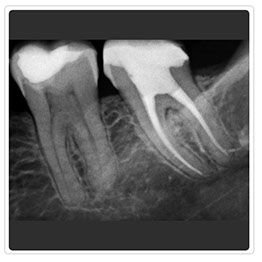

Radiografía Retroalveolar

Radiografía Control Endodoncia

Radiografía Intraoral